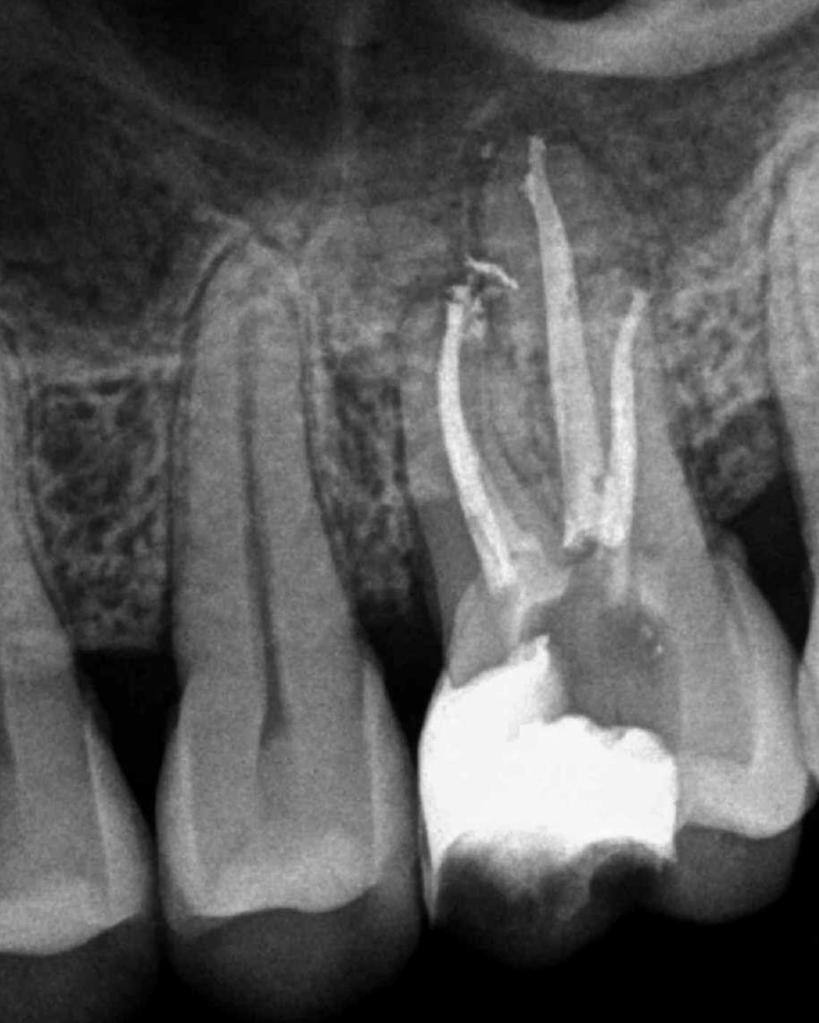

Molar superior anatomía compleja